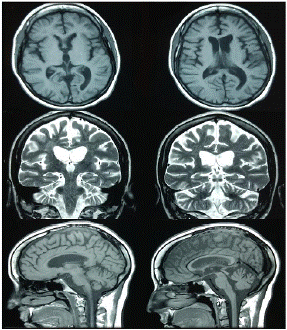

Se iniciaron, entonces, la terapia de rehabilitación neuropsicológica para el déficit cognitivo y la terapia fonoaudiológica centrada en el habla y el lenguaje, y se continuó con las fisioterapias motora y sensorial de soporte. En las sesiones de rehabilitación neuropsicológica, se emplearon rehabilitación viso-espacial, la terapia cognitivo-lingüística, corrección de apraxias, y entrenamiento de la memoria y las habilidades de atención. En la figura 2 se presenta la resonancia magnética de seguimiento.

Figura 2 Resonancia magnética de control cinco años después del síndrome de embolia grasa. Se observan cambios retráctiles difusos en el parénquima encefálico, ventriculomegalia compensatoria y malacia occipital izquierda con gliosis